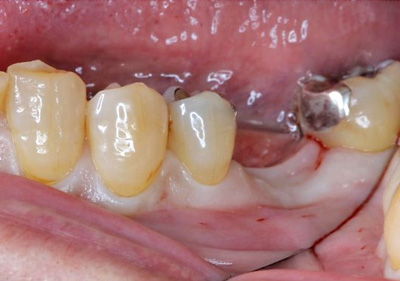

インプラント(骨造成術あり)

費用:50万円

治療期間:12ヶ月

メリット:隣の歯を削らない。歯と同じように噛める。

デメリット:骨、歯肉の状態では外科処置を数回行う場合あり。

治療中![]() |